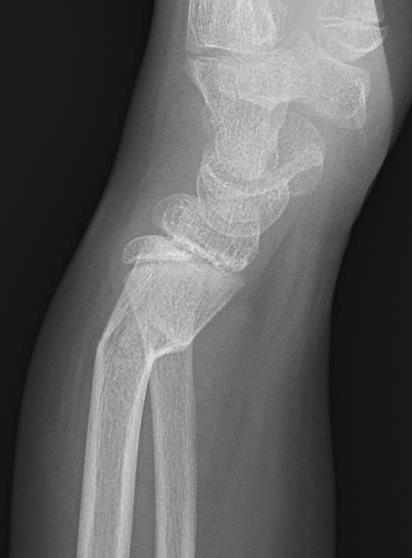

Physeal distal radius fracture

Physeal injuries

- risk growth plate arrest

- consider leaving < 50% displacement

- single reduction attempt only